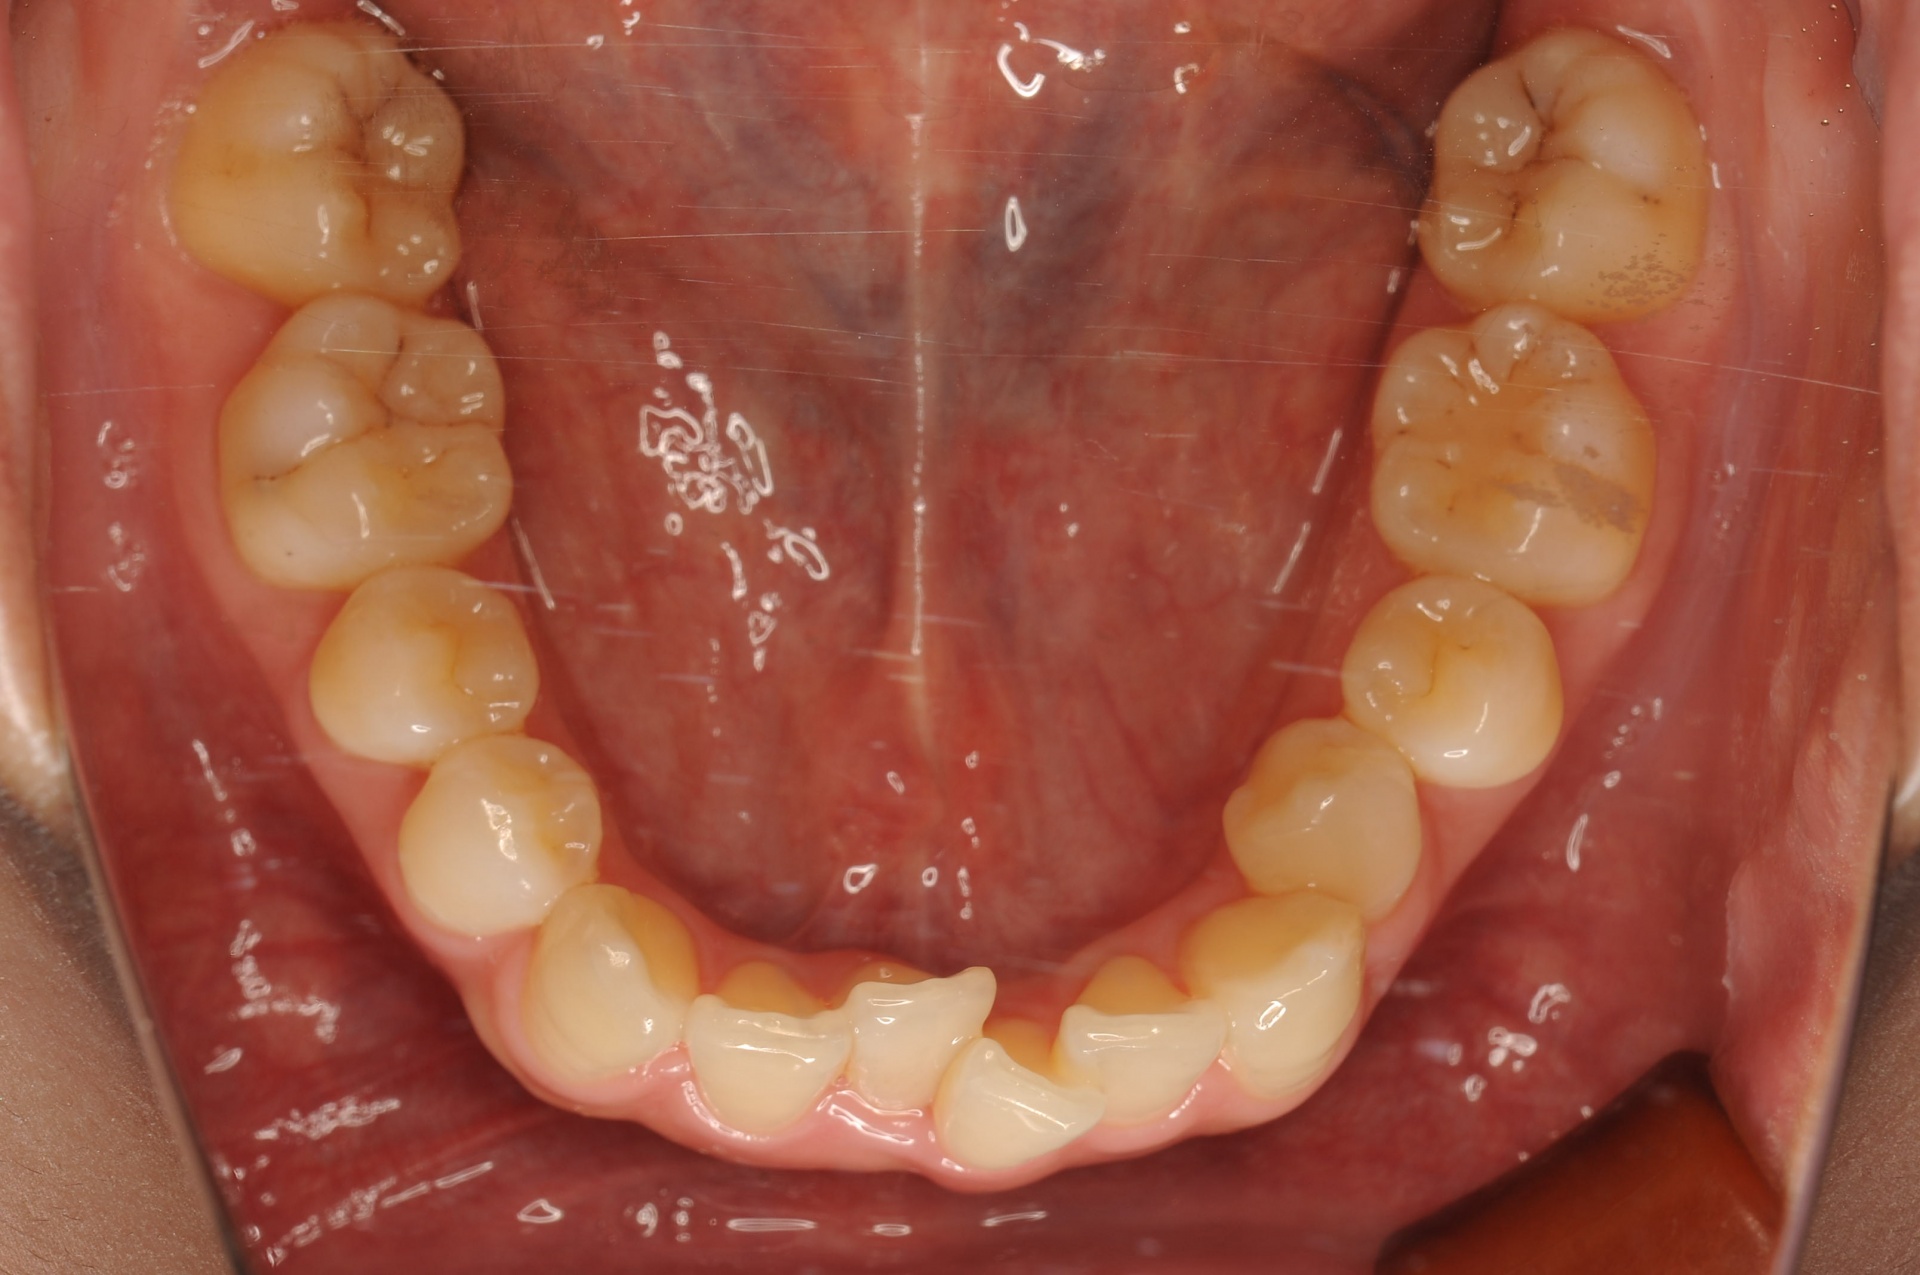

治療後

上下の正中は一致し、上顎両側犬歯は歯列内に誘導されました。奥歯の咬合関係は緊密で、再配列されたことにより機能・審美ともに改善されました。

| 治療内容 | 20代女性 上顎は叢生量が大きいため小臼歯抜歯のスペースを利用し、下顎は非抜歯で叢生を改善し各歯の再配列を行った |